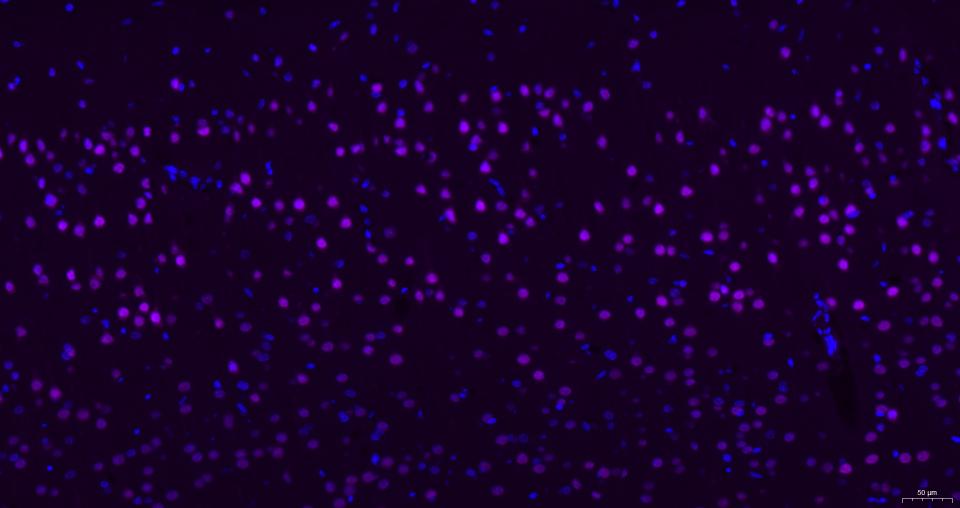

Paraformaldehyde-fixed, paraffin embedded Mouse brain; Antigen retrieval by boiling in sodium citrate buffer (pH6.0) for 15 min; Antibody incubation with AKT1 Monoclonal Antibody, Unconjugated(bsm-52010R) at 1:200 overnight at 4°C, followed by a Cy5 conjugated Goat Anti-Rabbit IgG (bs-0295G-Cy5)antibody at 37°C for 90 minutes, DAPI (blue, C02-04002) was used to stain the cell nuclei.